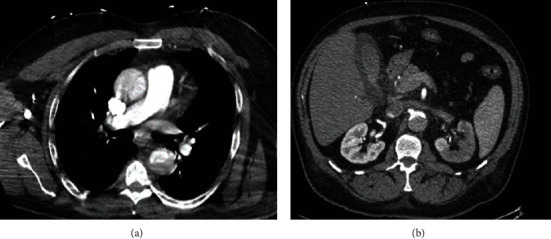

医源性主动脉夹层是经皮冠状动脉介入治疗(PCI)中一种罕见但可能致命的并发症。PCI术后的医源性主动脉夹层是罕见的,大多数病例报告夹层起源于冠状血管并扩散到升主动脉。本例剥离未累及冠状动脉,剥离从升主动脉延伸至降主动脉和髂血管。尽管经桡骨入路PCI的血管并发症比经股骨入路少,但仍可能发生明显的不良后果,需要及时干预。这个病例强调了高度不典型的医源性主动脉夹层在心导管置入后表现为急性肢体缺血。对于像我们这样的患者,由于整体预后不良,必须立即进行手术干预。

Iatrogenic aortic dissection is a rare but potentially fatal complication of percutaneous coronary intervention (PCI). Iatrogenic aortic dissection following PCI is rare with most cases reporting dissection originating within the coronary vessels with propagation into the ascending aorta. In this specific case, dissection was without coronary involvement, with dissection extending from the ascending aorta into the descending aorta and iliac vessels. Although PCI via radial approach is associated with fewer vascular complications than with femoral approach, significant adverse outcomes may still occur and require prompt intervention. This case highlights the highly atypical presentation of iatrogenic aortic dissection following cardiac catheterization presenting as acute limb ischemia. In such patients as with ours, immediate surgical intervention is necessary with overall poor prognosis.